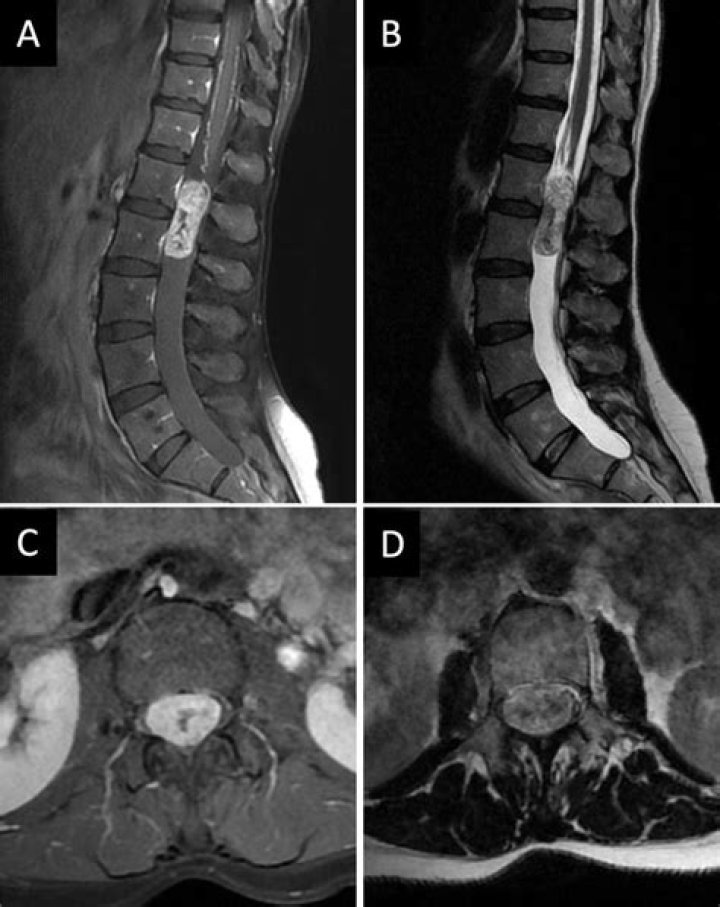

MRI is usually the preferred test to diagnose tumors of the spinal cord and surrounding tissues. A contrast agent that helps highlight certain tissues and structures may be injected into a vein in your hand or forearm during the test.

Can a spinal tumor be missed on an MRI?

Tumors in the thoracic spine were missed because the symptoms were similar to more common degenerative lumbar disorders and the absence of proper MRI screening. The possibility of thoracic spinal tumor should be kept in mind when unexplained low back pain persists in response to various treatments.